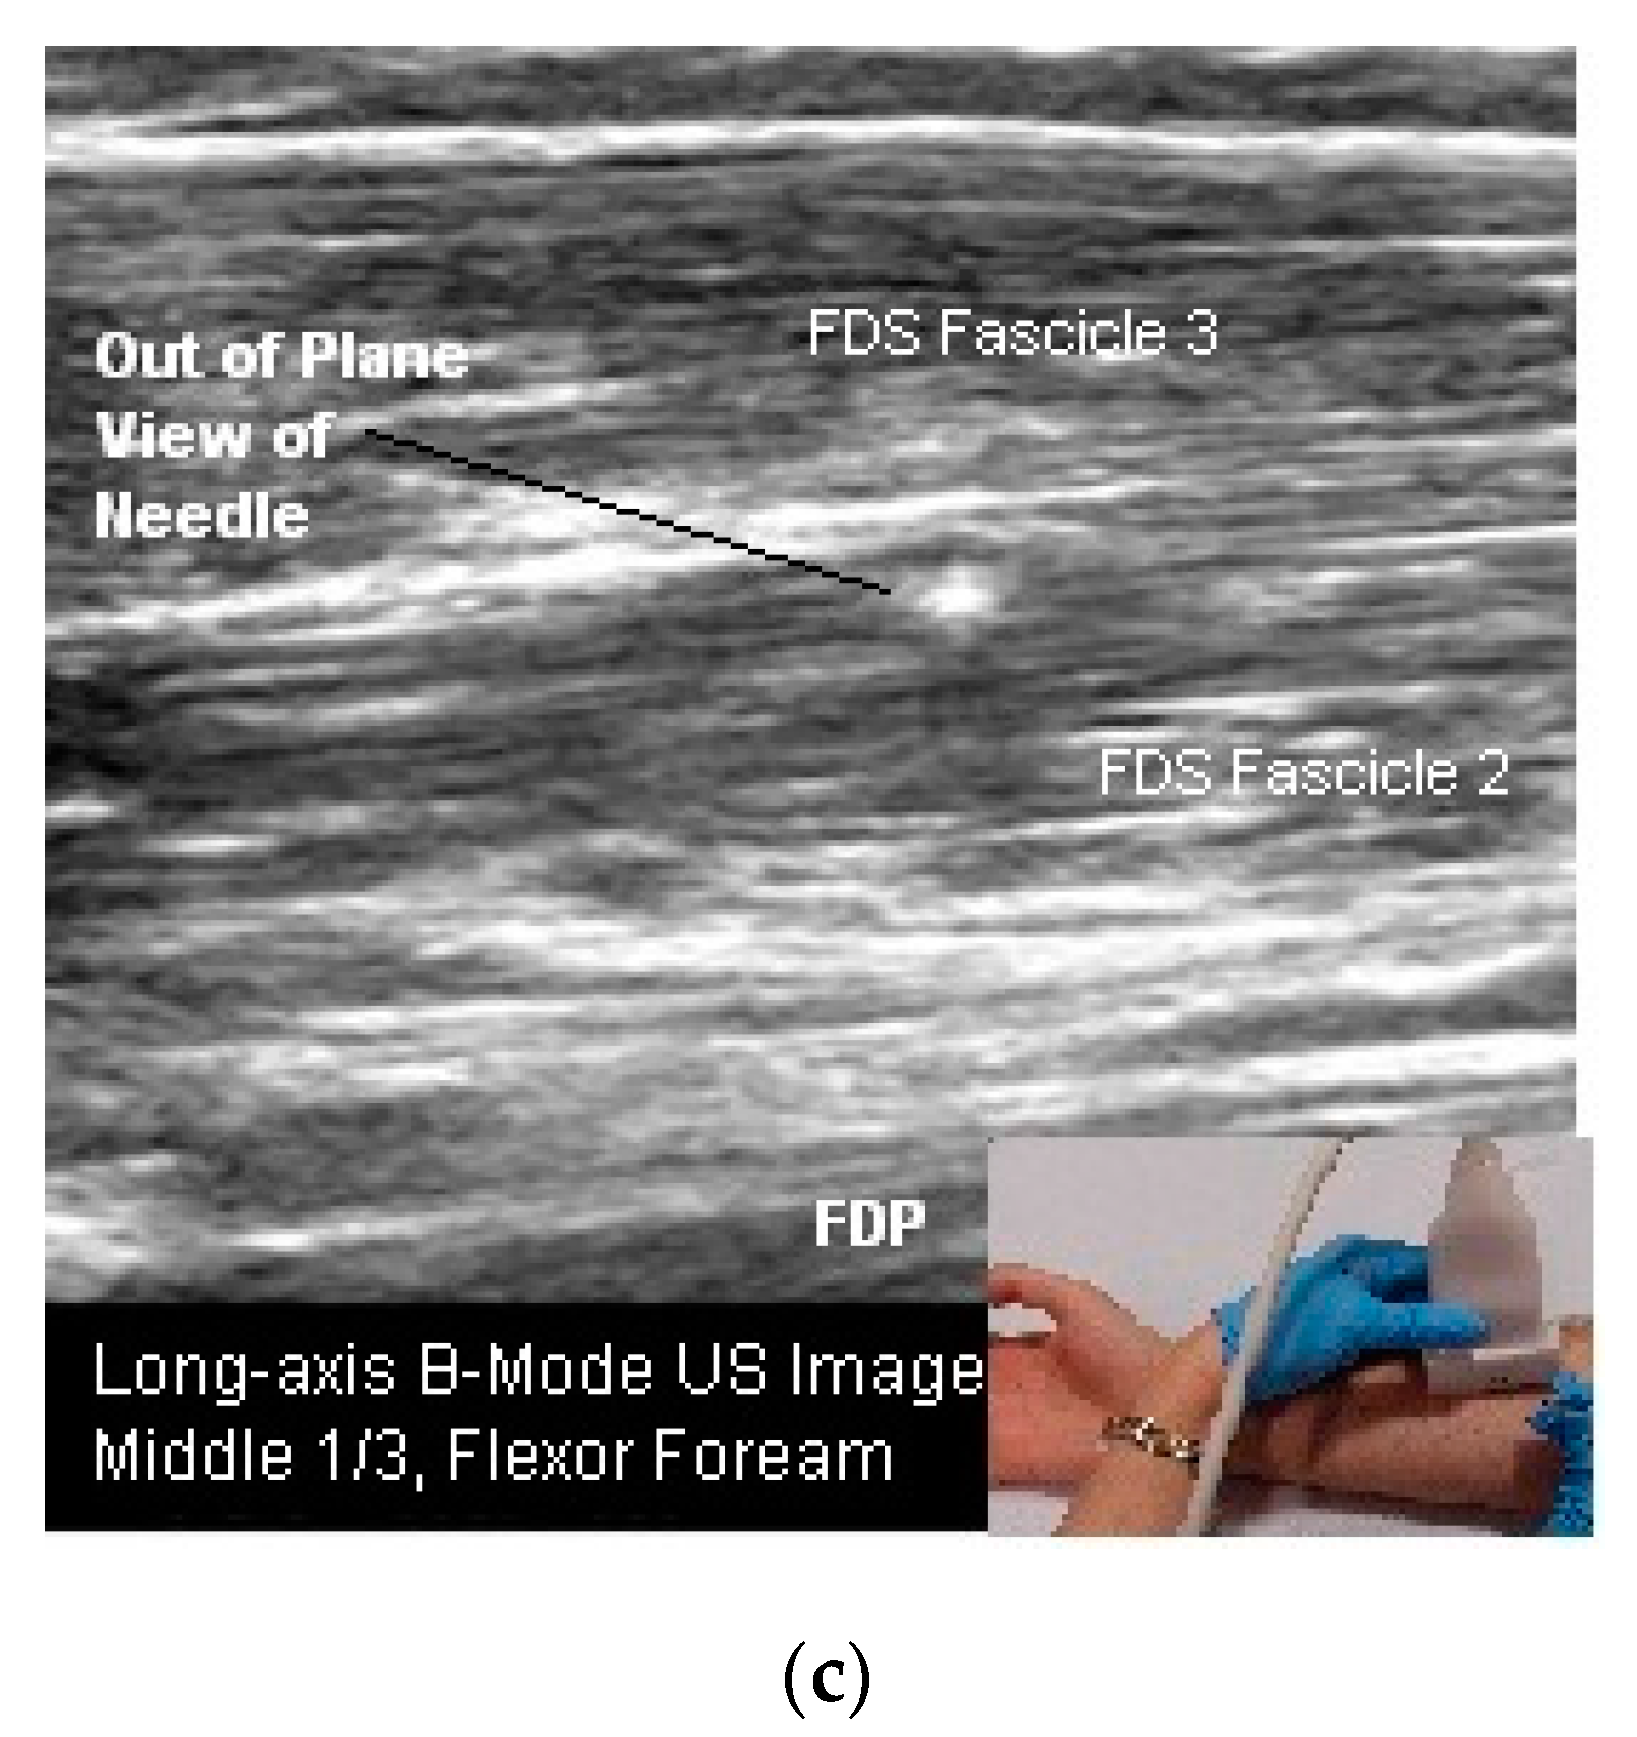

Figure 6.

(a) Long-axis B-mode US image, hand (palmar surface); (b) long-axis B-mode US image, anterior neck; (c) long-axis B-mode US image, flexor forearm.

Figure 7.

(a) Longitudinal B-mode US image, inplane injection; (b) transverse B-mode US image, out of plane injection medial gastrocnemius; (c) illustration, out of plane view of needle tip and shaft.

Two needle insertion techniques are utilized when performing US guided BoNT injections: Out of plane and in plane (Figure 6b,c and Figure 7a–c). There are advantages and limitations to each insertion technique. One technique may be superior to the other for a given patient or particular muscle/structure. Therefore clinicians should be familiar with both approaches [24,50,54].

- In Plane Technique (IPT). When using an IPT the needle is inserted along the length of the transducer (Figure 6b and Figure 7a). With the IPT, the entire needle and its tip is visualized, an advantage over the OPT. However, this technique can be challenging to perform because the sonographer must keep the needle within the narrow US beam. Another challenge is that optimal needle visualization requires that the needle be inserted and maintained in an orientation perpendicular to the US beam Figure 8a. When inserted at a steep or oblique angle, visualization of the needle may be lost due to needle anisotropy [24,50,54] (Figure 8b).